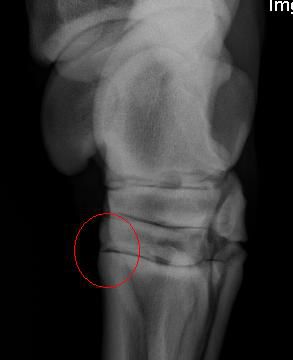

| Dire merci | Les radios! Jarret droit ![]() jarret gauche ![]() droit ![]() gauche ![]() droit ![]() gauche ![]() |

| Dire merci | Bon poru tes radios je trouve que c'est quand même bien visible les ostéophytes qu'il a. Donc pour la gestion, veiller à la bonne complémentation en minéraux t vitamines, qui ait bien tout ce qu'il faut. Par contre je comprends pas bien l'intérêt du Tildren dans ce cas-là. Il n'a pas d'ostéolyse importante dans ses articulations, et le Tildren ne fait que permettre la production d'os. |

| Dire merci | elphe -> ![]() falco -> ouais les boules.. Mais bon pas non plus envie qu'il aille s'empoisonner avec trop d'engrais.. ![]() nenya -> merci pour ton avis! Ca peut etre du à quoi ce genre de trucs? Pourquoi ya de l'os qui a poussé là? Et en quoi ca peut le gener? Apparemment le tildren equilibre les ostéoblaste et clastes. Donc ca peut etre pas mal pour justement arrêter eventuellement la croissance de l'os à cet endroit qui n'a pas lieu d'être.. Enfin je suis ptetre à coté de la plaque, je sais pas :-/ |

| Dire merci | D'après ce que je lis sur le net, les ostéophytes sont causés par l'arthrose et pas l'inverse... Donc le traitement au Tildren pourrait limiter la prolifération de cette excroissance. Et donc il y a bien de l'arthrose à cet endroit de l'articulation, arthrose qui a causé cette excroissance osseuse (comme pour une fracture, le corps réagit face à l'arthrose en comblant avec de l'os). Fin bref, le Tildren ne me parrait pas complètement idiot dans ce cas là je trouve, d'après ce que j'ai lu et d'apres ce que mon véto m'a dit. |

| Dire merci | Bon sinon j'ai trouvé une radios d'un jarret "qui ne présente aucune anomalie", on voit pas bcp de différence qd meme... (outre le fait que la position de la jambe ne soit pas pareil, Ulys ayant le postérieur moins "sous lui" ![]() [img]http://www.photoservice.com/volumeLR/phs_volume20120316/62161040_15510243/m_232305190_0.jpg" alt="" /> Message édité le 24/03/12 à 12:53 |